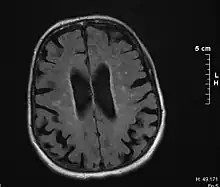

Binswanger's disease can usually be diagnosed with a CT scan, magnetic resonance imaging, and proton magnetic resonance spectrography in addition to clinical examination. Indications include infarctions, lesions, or loss of intensity of central white matter and enlargement of ventricles, and leukoaraiosis. A mini–mental state examination has been created to quickly assess cognitive impairment and serves as a screening test for dementia across different cultures.[13]

Leukoaraiosis refers to the imaging finding of white matter changes that are common in Binswanger disease. However, leukoaraiosis can be found in many different diseases and even in normal patients, especially in people older than 65 years of age.[5]

There is controversy whether leukoaraiosis and mental deterioration actually have a cause and effect relationship. Research has shown that different types of leukoaraiosis can affect the brain differently, and that proton magnetic resonance spectroscopy would be able to distinguish the different types more effectively and better diagnose and treat the issue.[9] Because of this information, white matter changes indicated by magnetic resonance imaging or computerized tomography cannot alone diagnose Binswanger disease, but can aid to a bigger picture in the diagnostic process. There are many diseases similar to Binswanger's disease including CADASIL syndrome and Alzheimer's disease, which makes this specific type of white matter damage hard to diagnose.[5] Binswanger disease may be diagnosed by a team of experts including a neurologist and psychiatrist to rule out other psychological or neurological problems.[3] Because doctors must successfully detect enough white matter alterations to accompany dementia as well as an appropriate level of dementia, two separate technological systems are needed in the diagnosing process.

Much of the major research today is done on finding better and more efficient ways to diagnose this disease. Many researchers have divided the magnetic resonance imaging of the brain into different sections or quadrants. A score is given to each section depending on how severe the white matter atrophy or leukoaraiosis is. Research has shown that the higher these scores, the more of a decrease in processing speed, executive functions, and motor learning tasks.[14][15] Other researchers have begun using computers to calculate the percentage of white matter atrophy by counting the hyper-intense pixels of the magnetic resonance images. These and similar reports show a correlation between the amount of white matter alterations and the decline of psychomotor functions, reduced performance on attention and executive control.[16][17] One type of technology is called susceptibility weighted imaging (SWI) which is a magnetic resonance technique which has an unusually high degree of sensitivity and can better detect white matter alterations.[18]